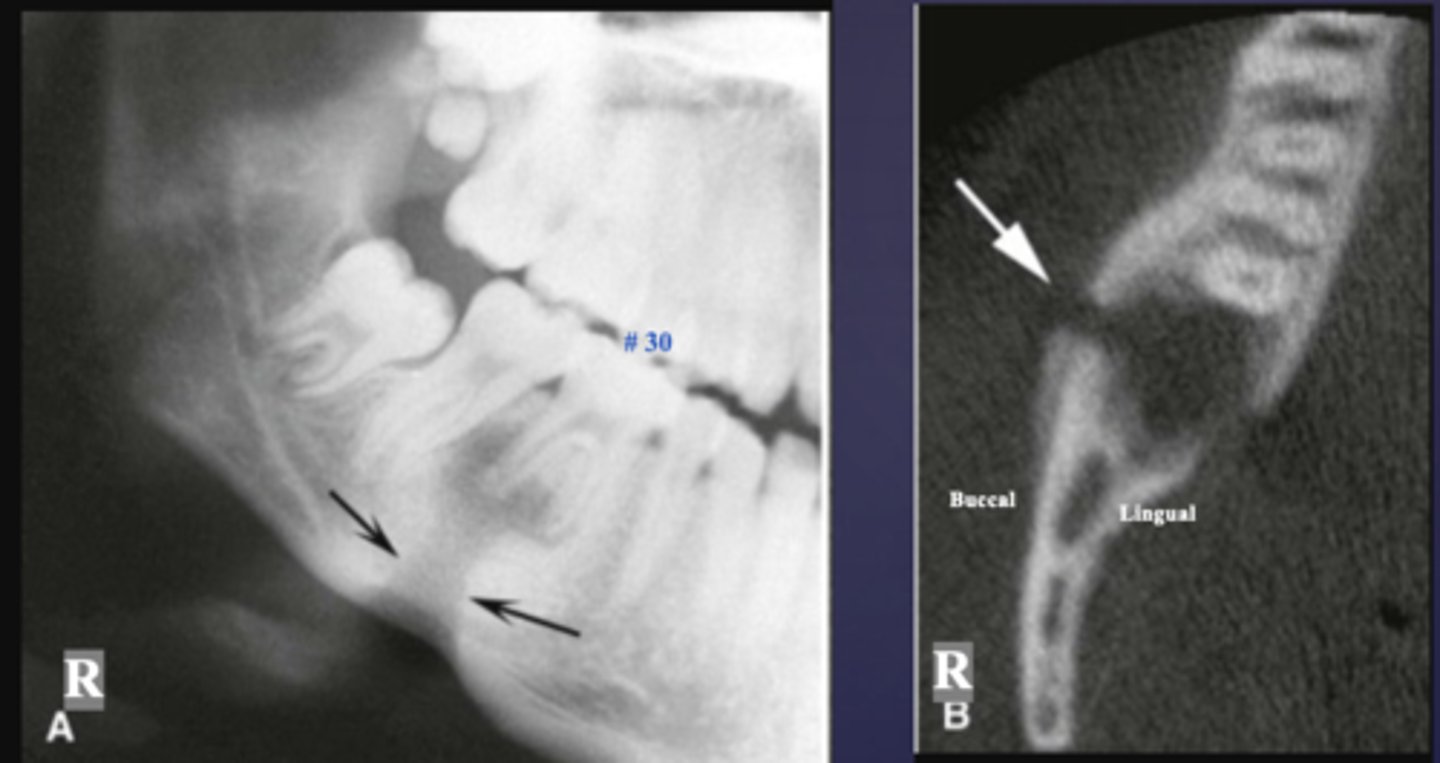

What is the black arrow pointing at?

sequestrae

What is the white arrow pointing at?

periosteal reaction

periosteal reaction (increased bone density)

sequestra

What phase of osteomyelitis does this show?

acute (multiple sequestrae)

What is the imaging method of choice for osteomyelitis

CBCT